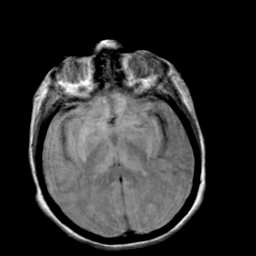

Creutzfeld-Jakob disease: proton density-weighted MR -- Slice #12

[Home][Help][Clinical] Slice 12